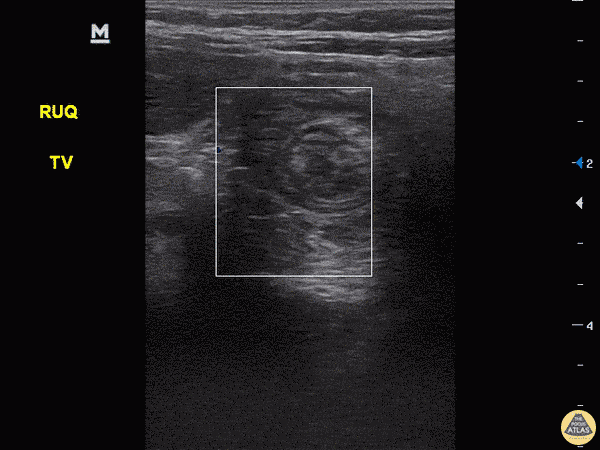

Peds-Gastrointestinal - Intussusception with Target Sign

4-year-old child with vomiting since yesterday, seen in urgent care and was reassured. Today continued vomiting and mother came to ED. Mild tenderness over RUQ. POCUS completed revealing intussusception. Target, Bulls Eye or Doughnut sign seen in the right upper quadrant, the most common region for an ileo-colic intussusception. Dr. Sathya Subramaniam, Pediatric EM Fellow - Kings County/SUNY Downstate